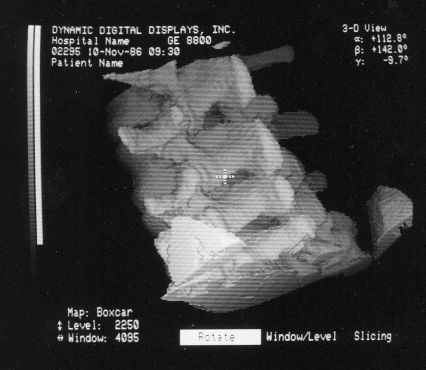

These photos of the Voxelscope II screen are typical of the types of rendering provided by the system.

Voxelscope II Screen Shots. Combination of 3-D Shaded Surface, Multiplanar Reformatting, and Segmentation